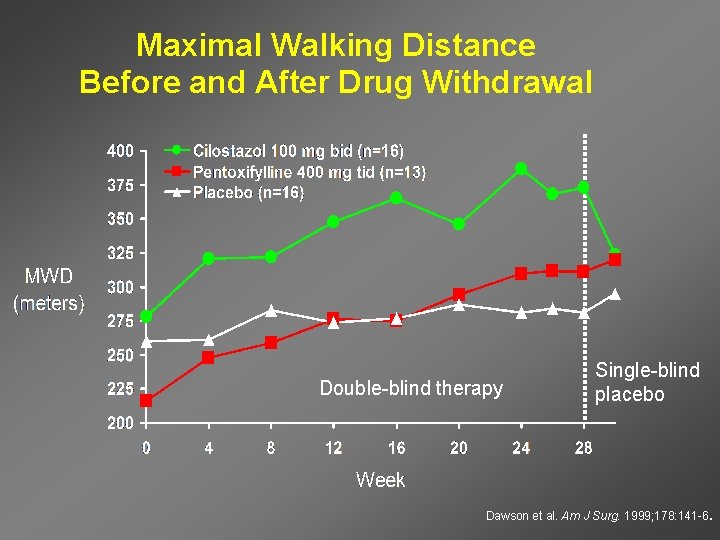

Maximal Walking Distance Before and After Drug Withdrawal Double-blind therapy Single-blind placebo Dawson et al. Am J Surg. 1999; 178: 141 -6.